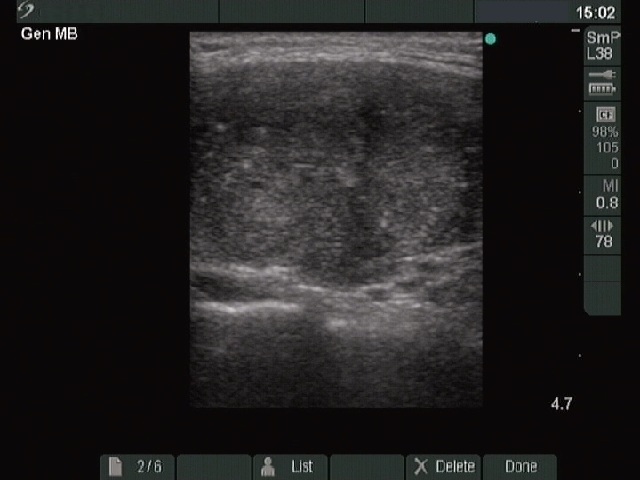

Ultrasonography : there was a moderately hypoechogenic inhomogeneous nodule with microcalcifications in the right lobe. The borders of the nodule were blurred. The intranodular blood flow was increased.